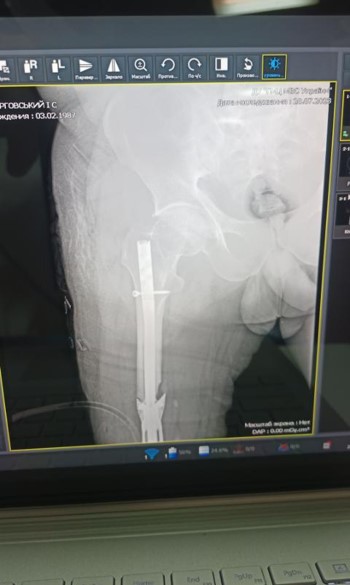

Хворий Г.58 остеосаркома стегнової кістки

Проектування та виготовлення індивідуальних аугментів для заміщення  дефектів суглобів: М, 48р, асептична нестабільність онкологічного ендопротеза . Заміщення дефекту індивідуальним аугментом та ревізійним ендопротезом , фіксація БІС, ПММА